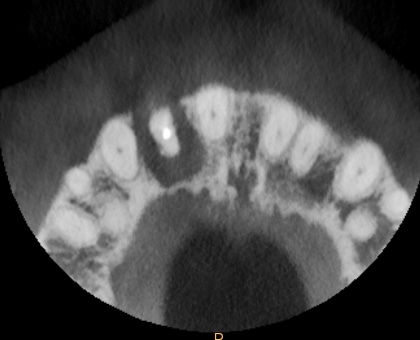

Healing was uneventful and following a seven-month maturation period, a CBCT scan confirmed the presence of the MinerOss®/autogenous bone graft and a favourable volume of bone. However, it was noted that the soft tissues covering the bone graft were thin with an absence of interdental papillae. It was determined that a connective tissue graft would be required as part of the next surgical procedure to improve the soft tissue volume and lead to the creation of papillae during the prosthetic stages.

Healing was uneventful and following a seven-month maturation period, a CBCT scan confirmed the presence of the MinerOss/autogenous bone graft and a favourable volume of bone.

The second surgery involved a palatal crestal incision and a full thickness flap elevation revealing good turnover of bone graft into host bone. A bone level implant was placed in an appropriate three-dimensional position completely surrounded by new bone and no additional bone grafting was required. A 4mm healing cap was placed.